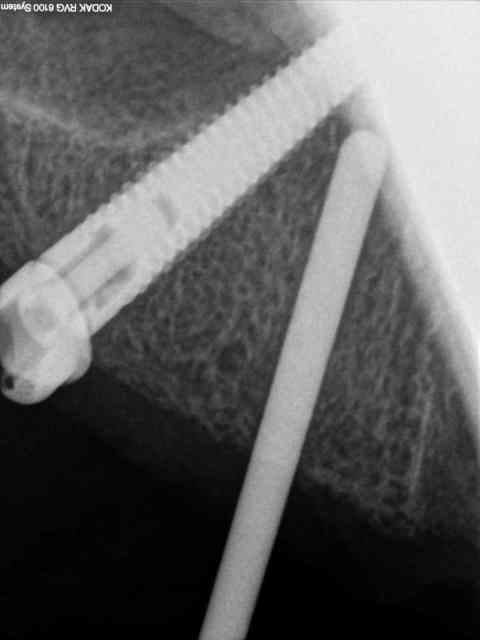

secteur 2:

on voit bien ici que cette méthode reste suffisamment précise pour longer le sinus sans le pénétrer.

je n'en demande pas d'avantage.

Cet implant pénètre de 5 à 6 mm dans le sinus.